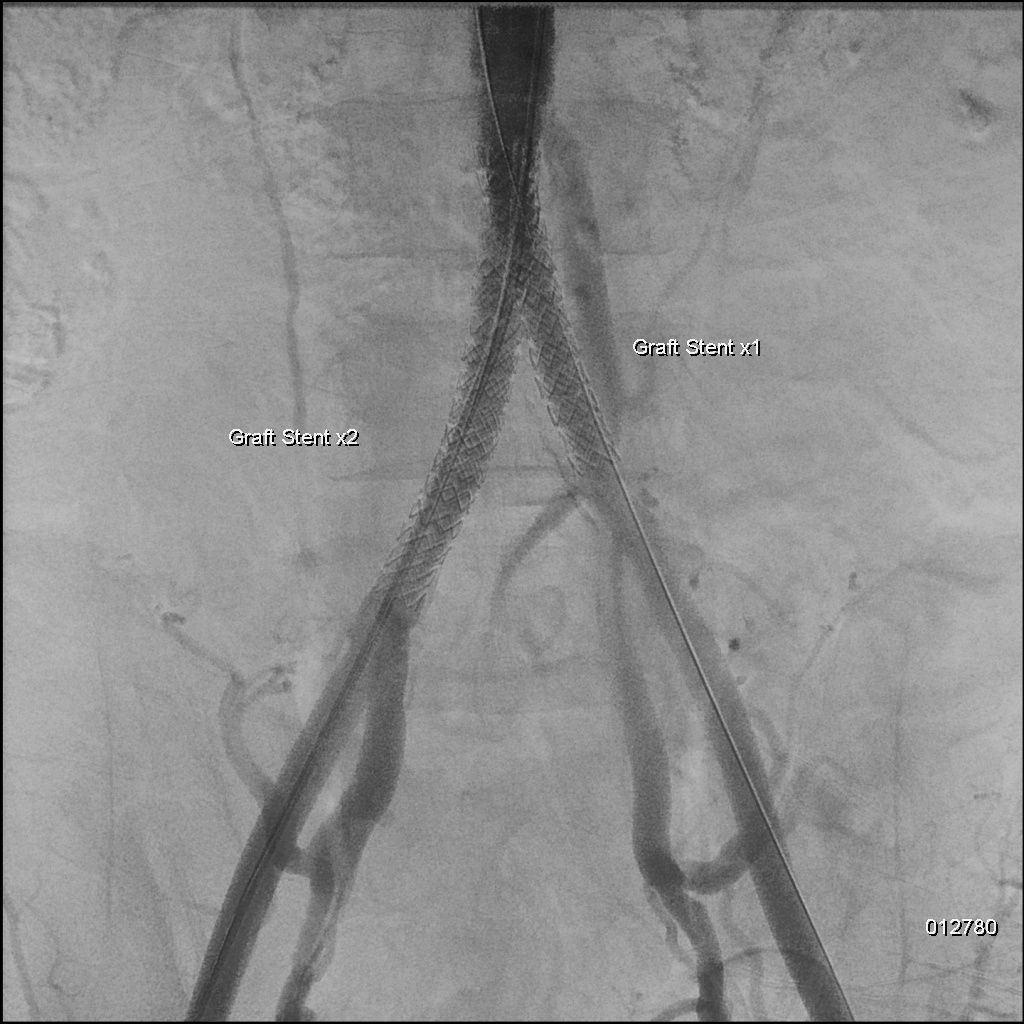

A 6F Mach1 MP guiding catheter waspositioned via aterial access. Wiring was performed sequentially with Gladius0.014¡È and Halberd 0.014¡È under NaviCross 0.018¡È catheter support, then switched to an Astato XS 40 for bettercontrol. Using a CSI microcatheter, the 0.018¡È system was exchanged for a 0.014¡È wire to performIVUS. IVUS initially could not advance but succeeded after predilatation withan Ultraverse 2.0 balloon. IVUS revealed that the lesion was locatedclose to the inferior mesenteric artery and provided accurate vessel sizing forappropriate stent selection. The system was then switched back to the 0.018¡È platform forintervention. Balloon dilatations were performed using Ultraverse 5.0 ¡¿ 80 mmfor the right and 7.0 ¡¿ 40 mm for the left common iliac artery, followed bysimultaneous kissing balloon inflation. Further expansion was achieved with Armada8.0 ¡¿ 80 mm balloons. Two VBX 8.0 ¡¿ 59 mm heparin-bonded stent grafts weredeployed in the right and left common iliac arteries. A subintimal flap belowthe right CIA stent edge required an additional VBX 8.0 ¡¿ 39 mm stent.Post-dilatation was performed with a Finestream S Plus 8.0 ¡¿ 40 mm andUltraverse 7.0 ¡¿ 80 mm balloon using the final kissing technique. Final angiography demonstrated well-expandedstents and excellent bilateral flow without residual stenosis or dissection.Both femoral access sites were closed with ProGlide devices, and the leftradial sheath was removed with manual compression.

Case Summary